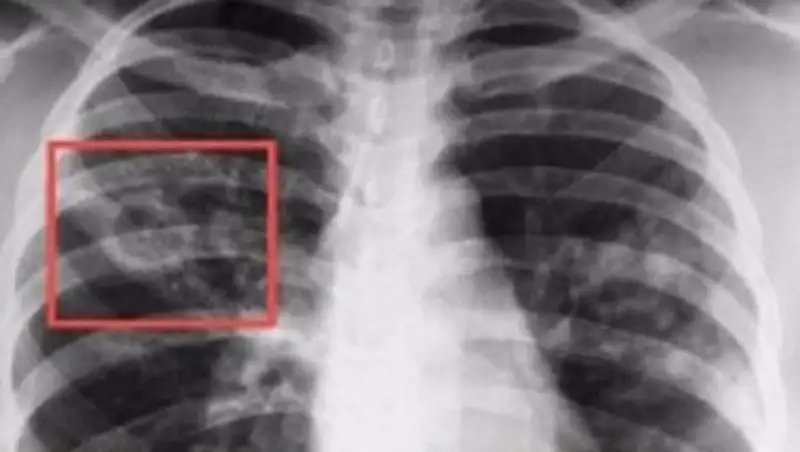

Понимание кавернозного туберкулеза почки

Раздел: Мудрость в деталях